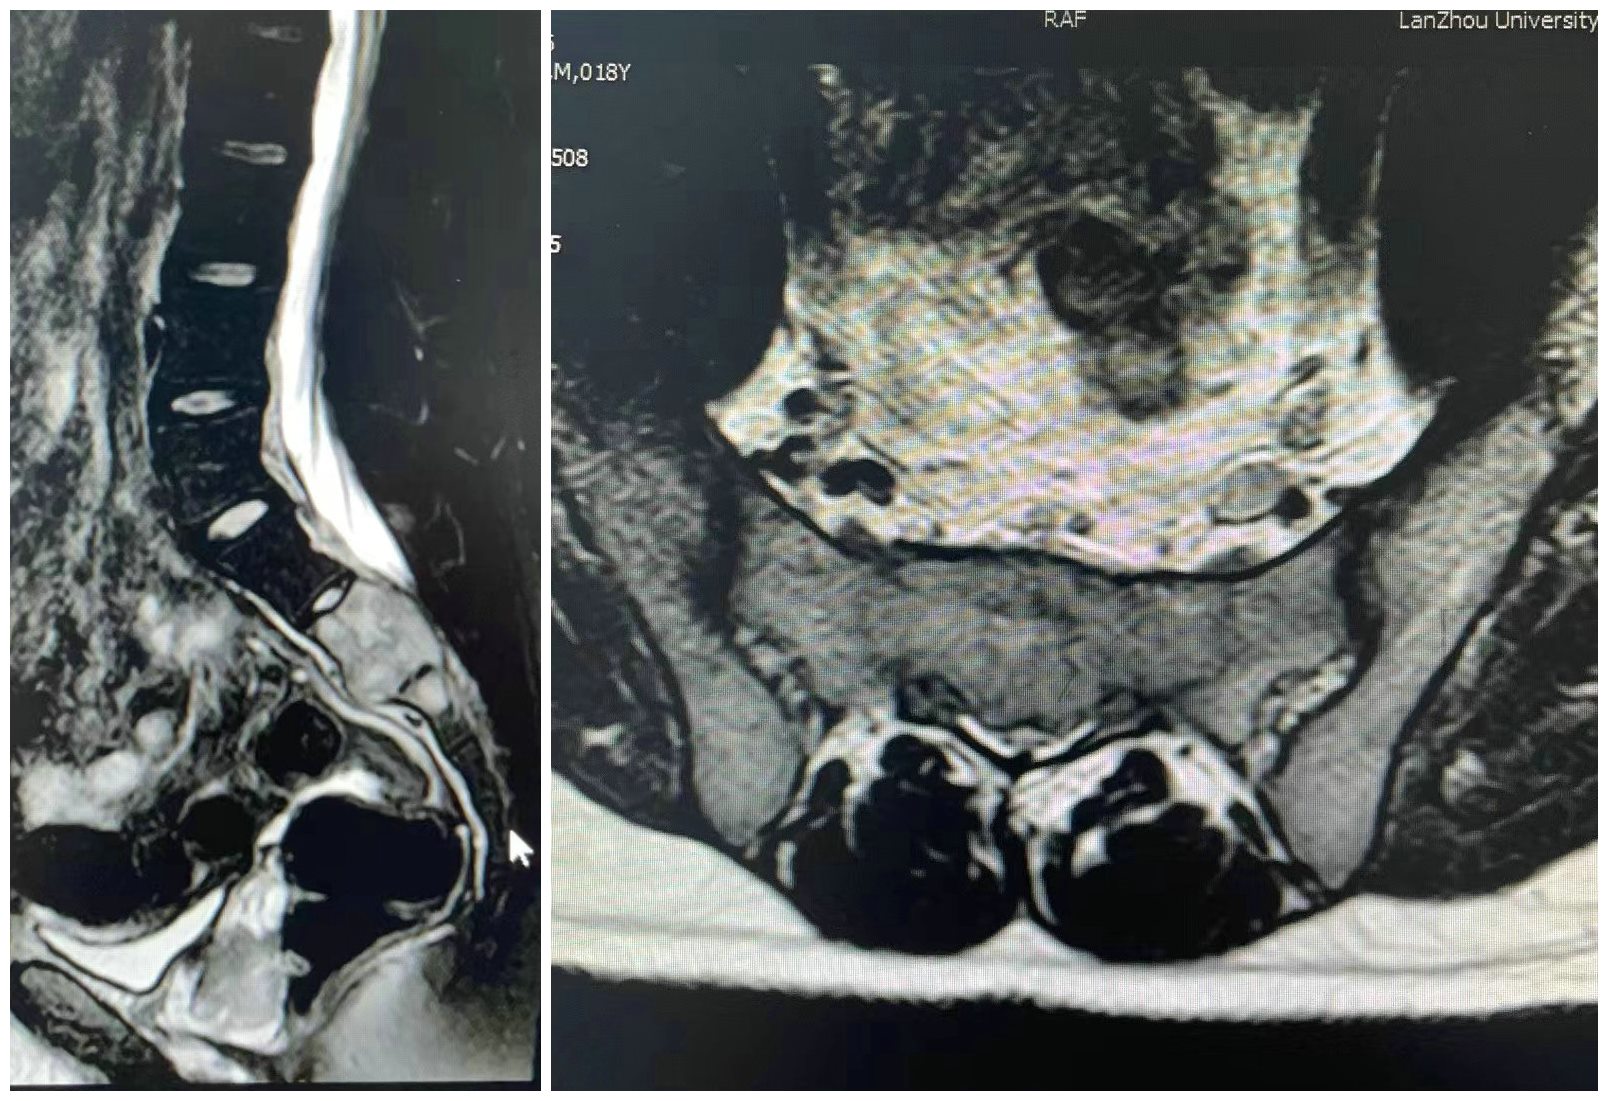

患者为18岁男性,因渐进性加重的骶部疼痛伴下肢无力半年收住入院(图片1、2)。入院后,完善相关检查,穿刺活检诊断为骶骨2、3巨细胞瘤,ki67达到60%,属于Campanacci3级(图片3)。影像显示瘤体侵袭骶骨2、3椎体,突破骶骨前方,向后突入椎管,压迫骶神经(图片1、2)。

图1 术前核磁共振